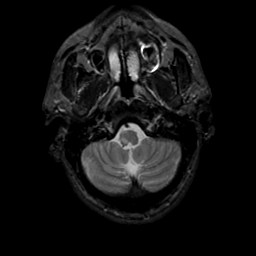

MR Study #20 October 6, 1991 -- Slice #6

[Home][Help][Clinical][Tour 1][Tour 2] Slice 6